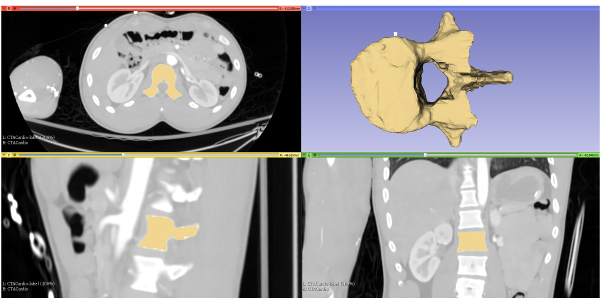

TRINOTA aims to help doctors assess patient specific treatment efficacy with the use of 3D visualization (Physical and Digital Models) of a patient's region of interest (ROI).

With the use of our Ultra High Resolution Professional Grade 3D Printer, we can produce physical models of the patient's ROI.